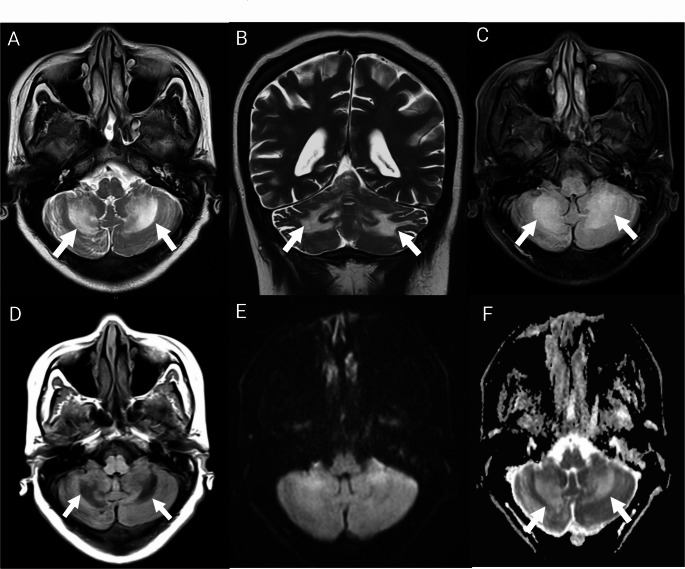

孤立的双侧小脑功能障碍作为HIV感染的初始表现:诊断挑战,病例报告和文献综述。

Isolated Bilateral Cerebellar Dysfunction as the Initial Manifestation of HIV Infection: A Diagnostic Challenge, Case Report, and Literature Review.